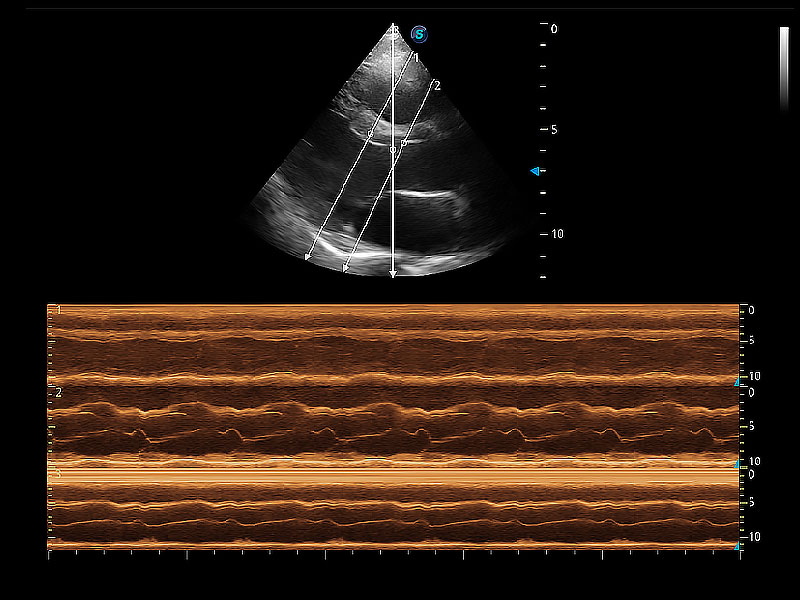

通過360度任意調(diào)節(jié)3條M型取樣線,在同一心動周期上觀察心臟不同位置的運動曲線,得到準確的心功能測量數(shù)據(jù),有效評估心肌運動及左心室功能。